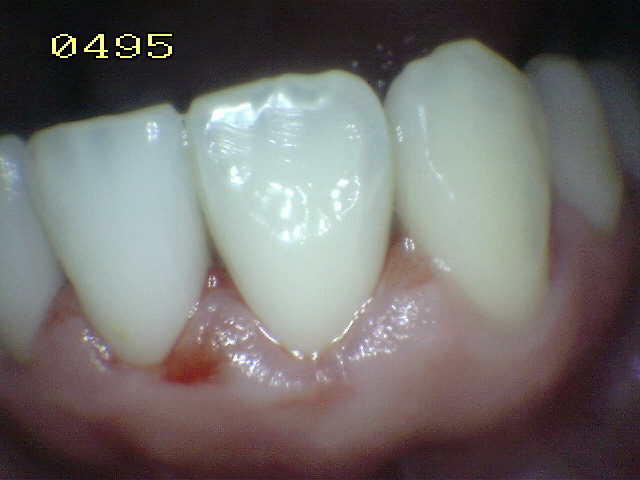

• Secar con jeringa triple por 5 segundos para realizar el examen visual en seco